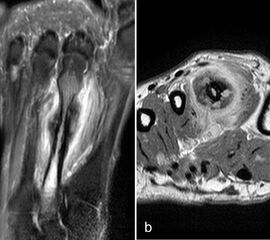

Typische Gichtmanifestation an der Großzehe mit Tophusstachel (Pfeil) und großem Tophus, in welchem Uratablagerungen identifiziert werden können (Pfeilspitze). T1-gewichtete Sequenz vor (a) und nach (b) Kontrastmittelgabe, letztere mit Fettsuppression.

Abbildung 15

Dies erst recht, wenn diese Arthritis am Großzehen­grundgelenk auftritt (Abb. 15). In diesen Fällen sollte man den Verdacht auch dann aufrechterhalten, wenn die MRT nur eine unspezifische Entzündung zeigt und die Harnsäurewerte, die starken Schwankungen unterliegen können, nicht erhöht sind.

Spezifische MR Befunde finden sich erst bei der chronischen Gicht, wenn sich in T2 sehr signalarme Kristallablagerungen und Gicht-Tophi bilden. Letztere führen dann häufig zu den aus der Röntgendiagnostik bekannten gelenkfernen Erosionen.

Abbildung 15: Typische Gichtmanifestation an der Großzehe mit Tophusstachel (Pfeil) und großem Tophus, in welchem Uratablagerungen identifiziert werden können (Pfeilspitze). T1-gewichtete Sequenz vor (a) und nach (b) Kontrastmittelgabe, letztere mit Fettsuppression.